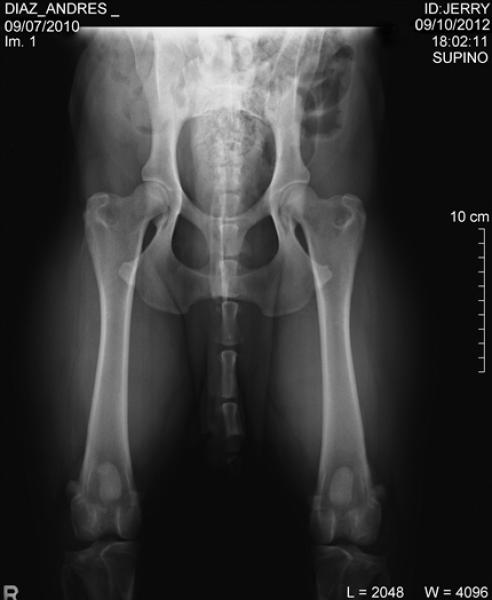

Incidencias de la Displasia de Cadera en el Rottweiler.

Seccion: Incidencias de la Displasia de Cadera en el Rottweiler.

La articulación de la cadera o coxofemoral, esta formada por la cabeza del fémur y el acetábulo, contribuyen a la estabilidad de dicha articulación el ligamento redondo, los músculos y la cápsula articula ...